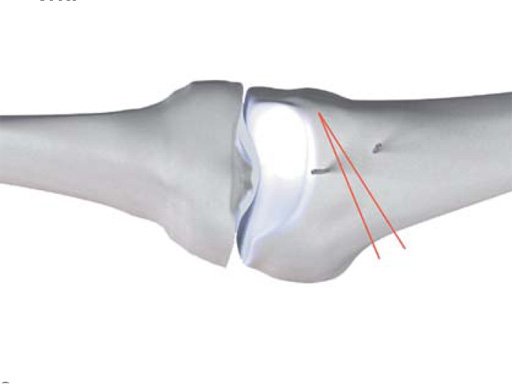

An anteromedial skin incision is used. This skin incision can be reused and expanded during subsequent knee surgery. The vastus medialis muscle is dissected from the septum, the medial patellofemoral ligament (MPFL) and the distal insertion of the vastus medialis muscle are partially incised. Two blunt Hohmann retractors are placed around the distal femur. The oblique osteotomy starts in the medial supracondylar area and ends in the lateral condyle, approximately 10 mm inside the lateral cortex. For guiding the closing wedge osteotomy of the distal femur a specific saw guide will be available soon. Alternatively, it is possible to use K-wires inserted under image intensifier control to mark the bone cuts. The saw cuts are made with retractors protecting the soft tissue and vessels. The wedge is removed and the height and depth of the osteotomy can be measured. At this time it is possible to make modifications concerning the wedge size. Closing the wedge must be done gradually by gentle compression of the lower leg laterally, and stabilizing the knee joint medially near the area of osteotomy. This may take several minutes to enable plastic deformation of the lateral cortex to close the osteotomy gap. Leg alignment is checked radiologically after closing with a rigid alignment bar positioned between hip and ankle center. The bar representing the weight-bearing line should pass the preoperatively defined mechanical axis. The plate is inserted from distal under the vastus medialis muscle. The distal drill holes are oriented in a 20 angle inclination on the frontal plane to avoid a posterior perforation of locking head screws in the distal femur. The distal four bolts are placed. A lag screw is positioned in the dynamic hole directly above the osteotomy for compression of the osteotomy site. The screw should be tightened carefully using the image intensifier. The plate is now fixed to the shaft with bolts monocortically, and the lag screw is replaced by a bolt bicortically. The wound is closed in layers after insertion of a drain. The patient is mobilized on the first day after surgery. Partial weight bearing is recommended for 6 weeks, active movement of the knee is enhanced. Biomechanical testing confirmed superior stability of medial closing wedge techniques as compared to lateral open wedge techniques and favourable axial and torsional loading characteristics of the TomoFix medial distal femur (MDF) plate. The plate is now available, as well as a booklet on the operative technique.